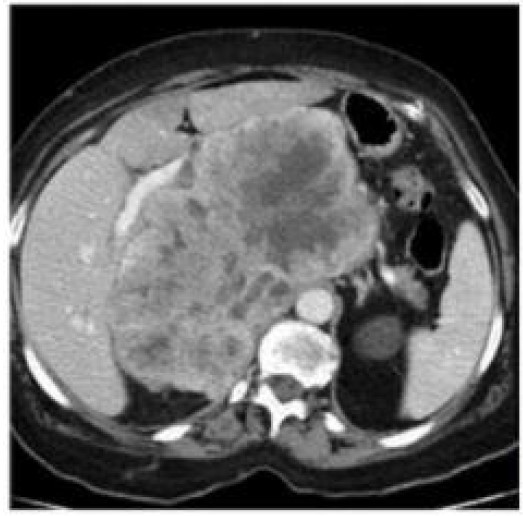

Diagnóstico e conduta

Leiomiossarcoma retroperitoneal - ressecção cirúrgica